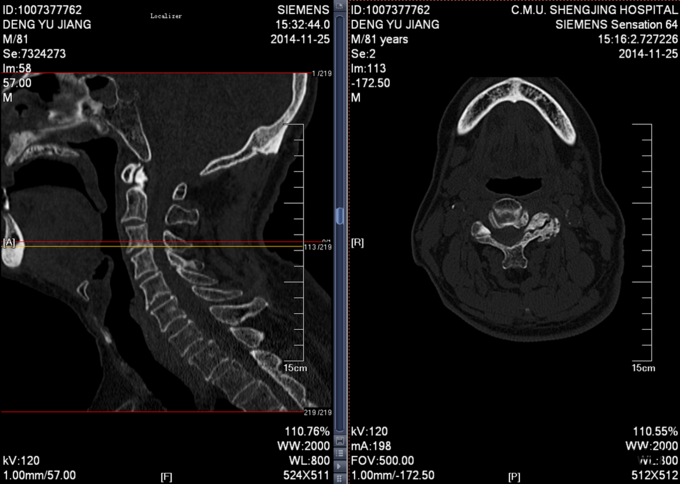

患者男,81岁,自述于1个月前出现双上肢感觉减退,发胀,以左侧为重,后来加重,左侧握力减退,于201医院就诊,行颈椎MR检查,提示为颈3-4、4-5间盘突出,为求进一步治疗就诊于我院,患者病来饮食、睡眠佳。大小便正常,体重无明显变化。

颈椎生理弯曲消失,活动度正常。双上肢感觉减退。双手握力(R5级,L4级),伸肘肌力(R5级,L5级),屈肘肌力(R5级,L5级),Hoffman(R-,L+)桡动脉搏动有力,末梢血运良。

诊断:颈椎病,颈椎间突出,高血压病 患者入院后完善相关检查,请相关科室及麻醉科会诊,医院医务部审批后,查无其他手术禁忌症,于全麻下行颈椎后路单开门椎管扩大减压侧块螺钉内固定术。术后给予患肢雾化祛痰,抗炎,消肿,营养神经,接骨等对症治疗。术后患者在颈领的保护下可下地行走,术后14天拆线后予以出院,